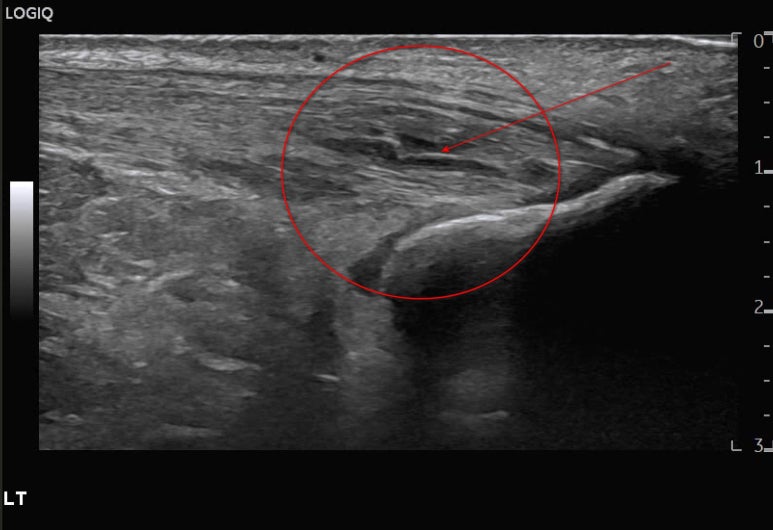

화살표친까만색 틈이 보이시나요?

정형외과에서

아킬레스건 염증이 심해지며

찢어지고 있다고

들으셨다고요.

힘줄이 완전히 파열되면

수술도 고려해봐야 됩니다.